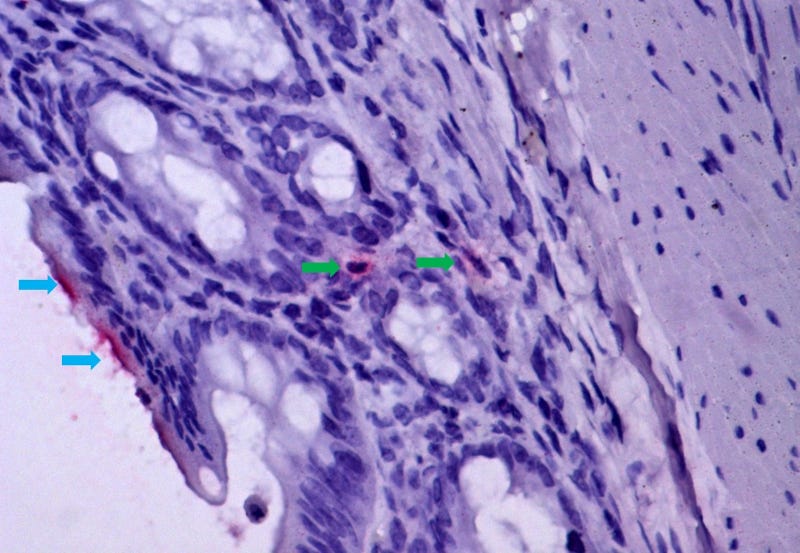

Mucosa intestinal de hamster infectado pelo vírus da febre amarela, demonstrando isquemia e translocação bacteriana, mecanismo de passagem de bactérias e seus produtos (marcados em vermelho, por imunohistoquímica) do lúmen intestinal (setas azuis) para a mucosa intestinal (setas verdes), atingindo a corrente sanguínea. O mesmo mecanismo de lesão ocorre em humanos com febre amarela fatal (imagem: Amaro Nunes Duarte Neto/HC-FM-USP)

“Observamos que a baixa de suprimento sanguíneo no intestino, que chamamos de isquemia mesentérica, acaba levando à passagem de produtos bacterianos do órgão – que possui a maior concentração da microbiota humana – para o sangue dos pacientes que desenvolveram a forma mais grave de febre amarela”, diz à Agência FAPESP Esper Kallás, professor da Faculdade de Medicina (FM) da USP e um dos autores do estudo.

“Inicialmente, essas observações foram tratadas como impressões anatômicas do patologista, mas ao analisar as lâminas constatei lesão vascular nos intestinos e no estômago, característica da falta de irrigação. A lesão vascular da mucosa gastrointestinal permite a passagem de bactérias do lúmen intestinal para o sangue e o fígado, agravando o dano inicial pelo vírus da febre amarela e levando ao óbito”, explica Duarte.

Para validar os achados, os pesquisadores da USP associaram-se ao professor Adam Bailey, da Universidade de Wisconsin-Madison, que desenvolveu um modelo experimental de hamster infectado pelo vírus. As análises dos tecidos animais evidenciaram um quadro semelhante ao humano, com hemorragias e trombos na parede intestinal.

“A entrada de bactérias no sangue dos animais mostrou que a translocação é um mecanismo progressivo na evolução da febre amarela grave”, afirma Duarte. Os pesquisadores pretendem agora analisar amostras de pulmões de pacientes fatais para entender os efeitos dessa translocação no órgão.